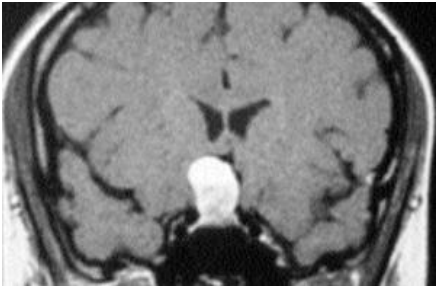

Observe a ressonância magnética, abaixo:

A imagem acima, indica, Cisto da bolsa de Rathke - RM com uso de gadolíneo, corte coronal. Observa-se massa hiperintensa, em T1 de crescimento: